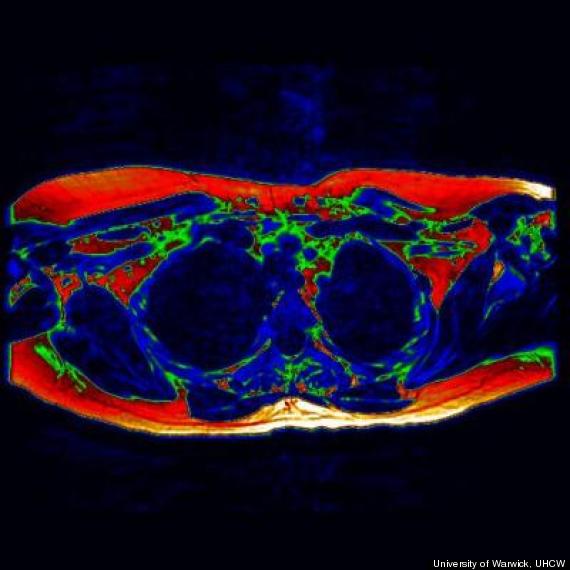

Investigadores de la Universidad de Warwick, en el Reino Unido, por primera vez han podido obtener evidencia de grasa parda en un adulto por medio de un estudio de Imagen por Resonancia Magnética, lo que es un paso importante en su conocimiento para aprender a activar su potencial en el control de peso.

«La Resonancia Magnética nos permite distinguir entre la grasa parda y la mejor conocida grasa blanca que la gente asocia con ganancia de peso, debido a la relación agua/grasa que es diferente en ambos tejidos,» dijo el Dr. Thomas Barber, investigador del Departamento de Salud Metabólica y Vascular en la Escuela de Medicina de Warwick en un comunicado de prensa. «Podemos usar las imágenes para destacar lo que llamamos ‘regiones de interés’ que pueden ayudarnos a formar una imágen de dónde está ubicada la grasa parda.»

En estudios anteriores, los investigadores han encontrado actividad de grasa parda por medio de PET (Tomografía por emisión de positrones), un estudio que requiere el uso de isótopos marcados y en el que los sujetos se tienen que exponer al frío para que la grasa parda se encuentre metabólicamente activa. La nueva técnica de Resonancia Magnética puede capturar imágenes tanto de grasa parda activa como inactiva, de forma que los científicos pueden tener una imágen más precisa de dónde se localiza.